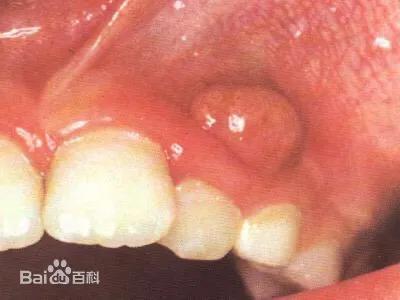

根尖周炎炎症不加以控制,则有可能会继续发展成为根尖周脓肿,此时急性期的咬合疼痛等症状较之前稍有缓解,根尖牙龈出可见鼓起的小脓包。此时治疗方式仍为根管治疗。